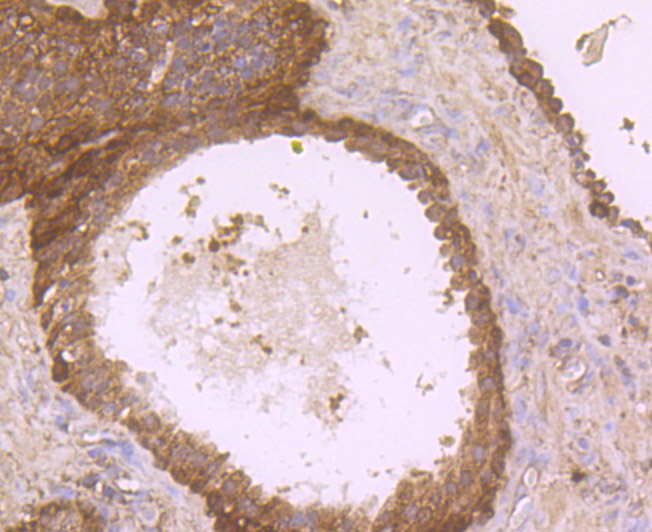

Immunohistochemical analysis of paraffin-embedded human prostate tissue using anti-DOCK4 antibody. Counter stained with hematoxylin.